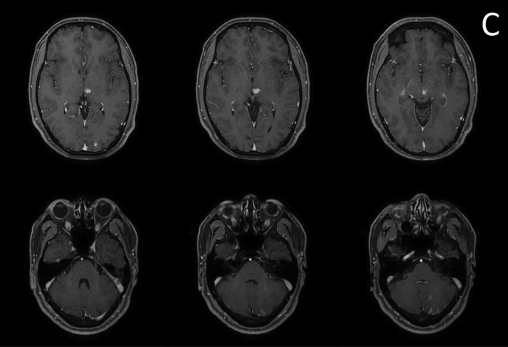

病例3:《Acute cerebral infarction of posterior circulation in a patient with vertebral artery fenestration deformity: A case report》发表于《Heliyon》杂志(IF 3.7)。患者是一名36岁男性,因“头晕、呕吐、行走不稳6小时”入院。外院颅脑MR提示左侧丘脑、左侧枕叶、左侧小脑多发不规则高信号病灶,我院颅脑MR增强检查证实左侧丘脑、左侧枕叶、左侧小脑多发急性脑梗死,头颈部CTA检查提示左椎动脉V2 -V3段开窗畸形。予抗血小板、调脂稳斑等治疗后,患者症状完全缓解,出院3个月随访时患者未出现新发脑梗死。本病例的罕见之处在于患者既往无任何脑梗死相关危险因素,排除了心源性栓塞、风湿免疫、血液系统疾病相关性卒中等其它可能,考虑患者急性脑梗死的病因为左椎动脉V2-V3段开窗畸形。

颅脑MR增强检查证实左侧丘脑、左侧枕叶、左侧小脑半球多发梗死